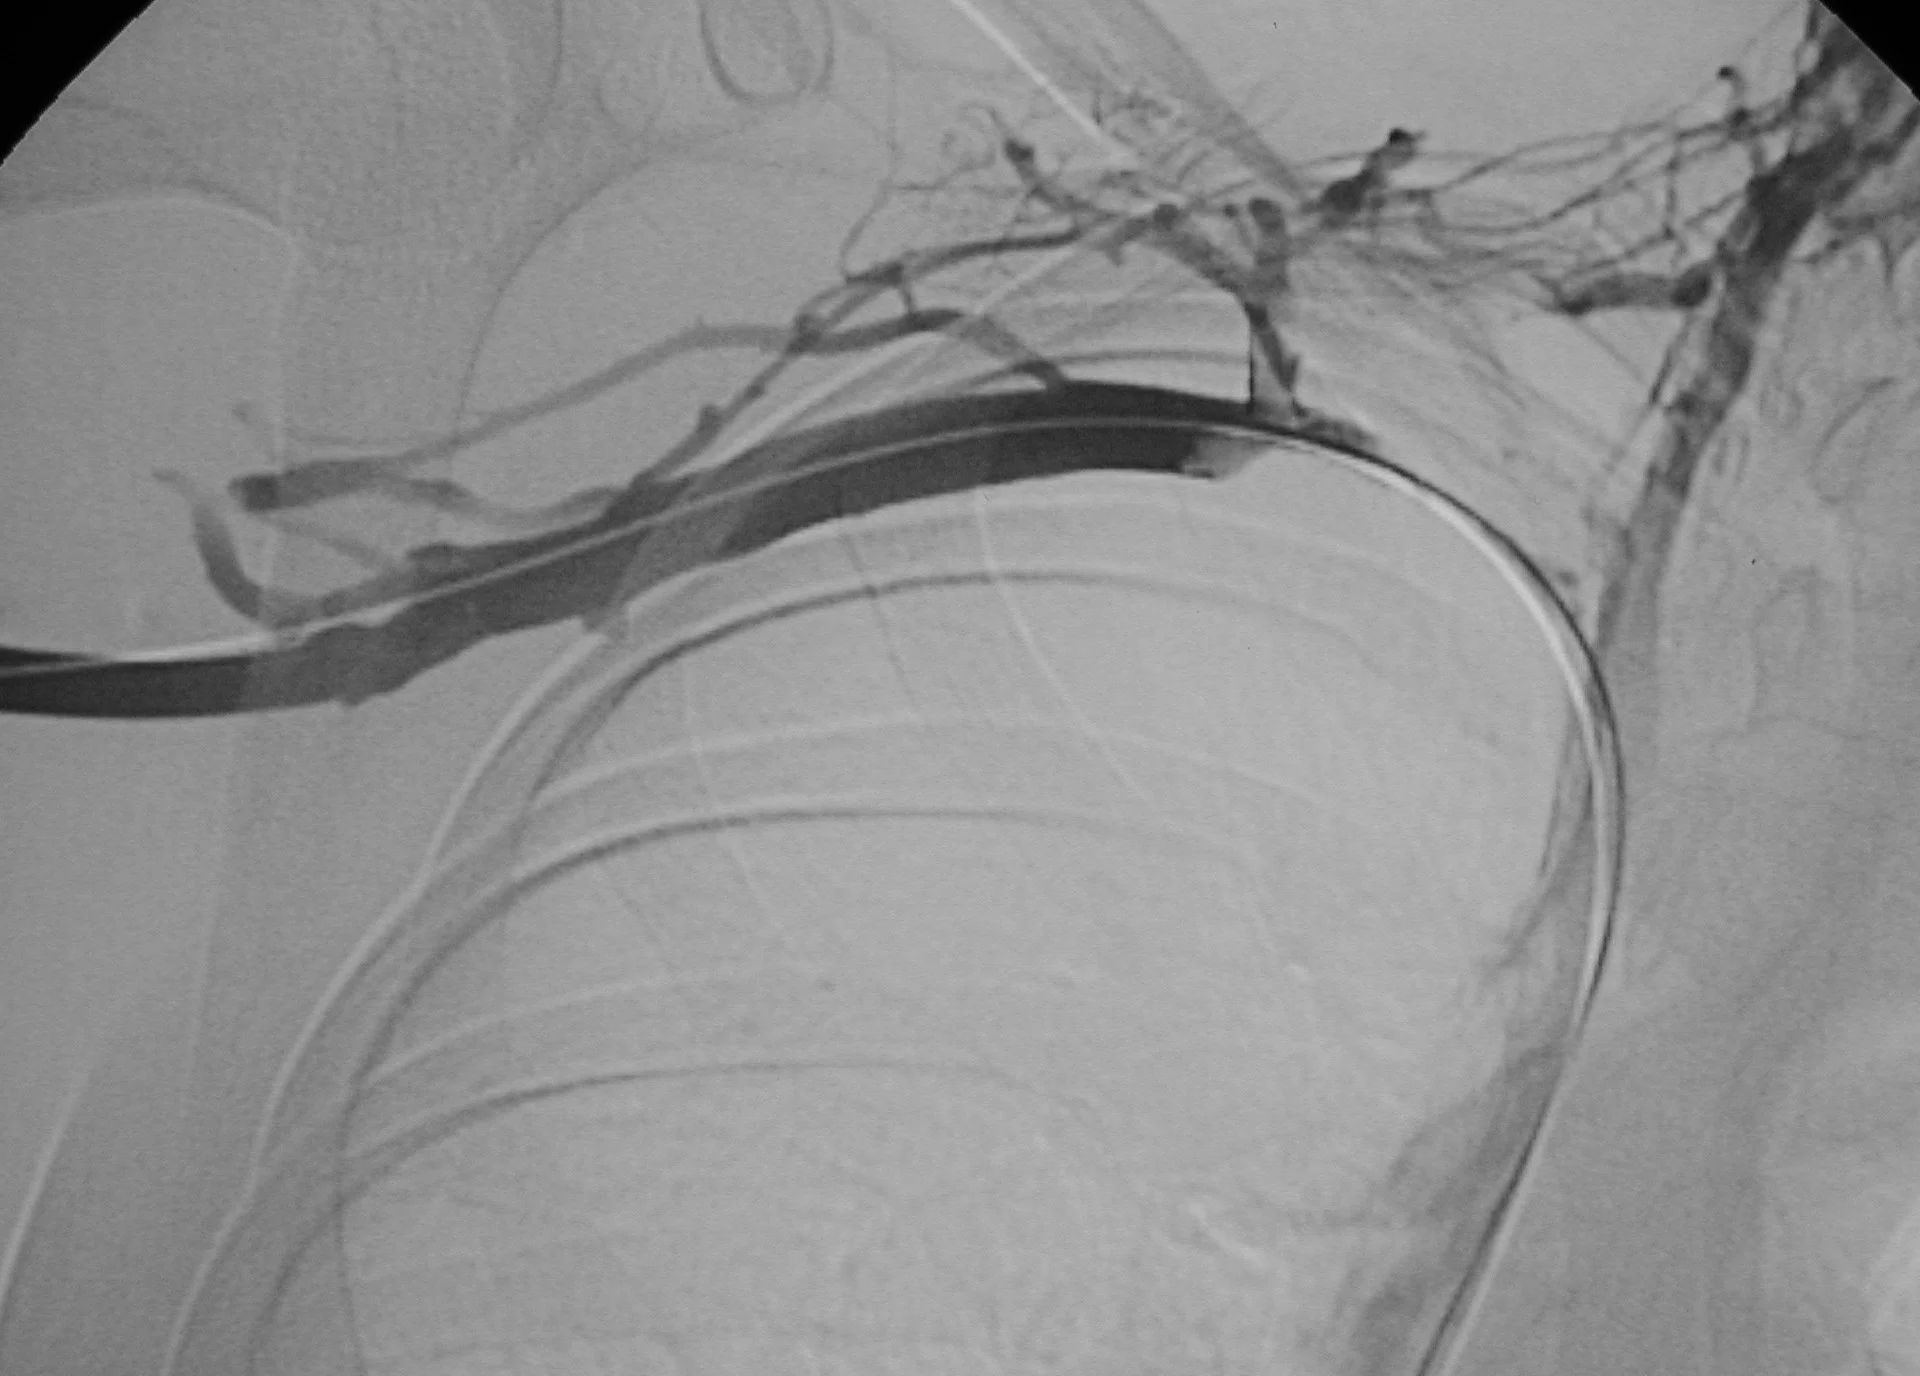

venous thromboembolic disease: Case 4

21 year old college basketball player who presents with right upper extremity swelling for 6 days.